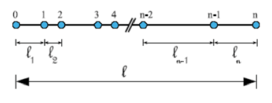

Boundary conditions from multiscale modeling of circulation: Another approach to impose the boundary conditions is to use reduced models, as 1D model or 0D (lumped) models. 1D and 0D models are mathematical models able to reproduce the systemic and pulmonary circulation. Figure 10 shows a standard approach to provide realistic local boundary conditions for 3D CFD simulations at the specific arterial domain using 1D models of the entire arterial tree and 0D models at the distal ends[83]. 1D model solves the Navier-Stokes equations under some assumptions (see appendix 9) and lumped models (0D models) can be derived from electrical circuit analogies where blood flow is represented by the current and arterial pressure by the voltage. Usually the electrical components of these circuits are resistances, inductances and capacitors. Where resistances represent arterial and peripheral resistance that occur as a result of viscous dissipation inside the vessels, capacitors represent volume compliance of the vessels that allows them to store large amounts of blood, and inductors represent inertia of the blood[75]. The values of these electrical components can be estimated from physical data of the subject [84][85]. This approach is quite used because it is capable to account for the effect of local pathological conditions on the whole circulatory system, providing realistic boundary conditions for the 3D problem [75][79][86].